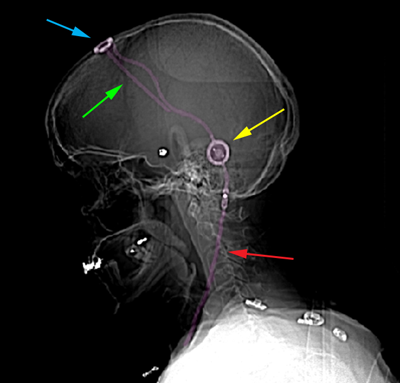

Σύστημα κοιλιοπεριτοναϊκής παροχέτευσης με βαλβίδα. Κοιλιακός καθετήρας (εισέρχεται στο κοιλιακό σύστημα του εγκεφάλου) με πράσινο βέλος, ρεζερβουάρ Ε.Ν.Υ. με κυανό βέλος, βαλβίδα ρύθμισης της πίεσης με κίτρινο βέλος, περιτοναϊκός καθετήρας με κόκκινο βέλος. |

Θεραπεία Ο αποφρακτικός υδροκέφαλος απαιτεί άμεση θεραπεία, ή με εξωτερική παροχέτευση, ή δημιουργία παράκαμψης του Ε.Ν.Υ. ή ανάταξη της απόφραξης αν αυτό είναι δυνατό. Η εξωτερική παροχέτευση του Ε.Ν.Υ. τοποθετείται σε υπερεπείγουσες καταστάσεις και είναι προσωρινή. Γίνεται με την τοποθέτηση ενός λεπτού σωλήνα από σιλικόνη στο κοιλιακό σύστημα του εγκεφάλου με κρανιονάτρηση (διάνοιξη μικρής οπής στο κρανίο) και σκοπό έχει να μειώσει την ενδοκράνια πίεση παροχετεύοντας Ε.Ν.Υ. Η εξωτερική παροχέτευση μπορεί να τοποθετηθεί και στην οσφύη με απλή παρακέντηση μόνο εάν ο υδροκέφαλος είναι επικοινωνούντος τύπου. Η μόνιμη παράκαμψη της φυσιολογικής παροχέτευσης του Ε.Ν.Υ. πραγματοποιείται είτε με τοποθέτηση συστήματος κοιλιοπεριτοναϊκής παροχέτευσης με βαλβίδα (το οποίο μεταφέρει Ε.Ν.Υ. από το κοιλιακό σύστημα του εγκεφάλου στην περιτοναϊκή κοιλότητα), είτε με ενδοσκοπική τρίτη κοιλιοστομία εγκεφάλου (η οποία είναι η διάνοιξη μιας οπής στο κοιλιακό σύστημα του εγκεφάλου με σκοπό την τεχνητή παροχέτευση Ε.Ν.Υ. προς τις βασικές δεξαμενές του εγκεφάλου), είτε με σύστημα οσφυοπεριτοναϊκής παροχέτευσης Ε.Ν.Υ. (το οποίο μεταφέρει Ε.Ν.Υ. από τον οσφυϊκό μηνιγγικό σάκο στην περιτοναϊκή κοιλότητα). Η τελευταία μέθοδος είναι κατάλληλη μόνο για ασθενείς με υδροκέφαλο επικοινωνούντος τύπου. Στον αποφρακτικό υδροκέφαλο πρέπει πάντα να εξαιρείται, όταν είναι εφικτό, η αιτία της απόφραξης, και αυτό καθιστά την λύση των παρακάμψεων στην παροχέτευση του Ε.Ν.Υ. όχι απαραίτητη, δίνοντας οριστική λύση στο πρόβλημα. Δες και ενότητες: Τοποθέτηση Συστήματος Παροχέτευσης ΕΝΥ (Βαλβίδα Εγκεφάλου) και Ενδοσκοπική Τρίτη Κοιλιοστομία. |